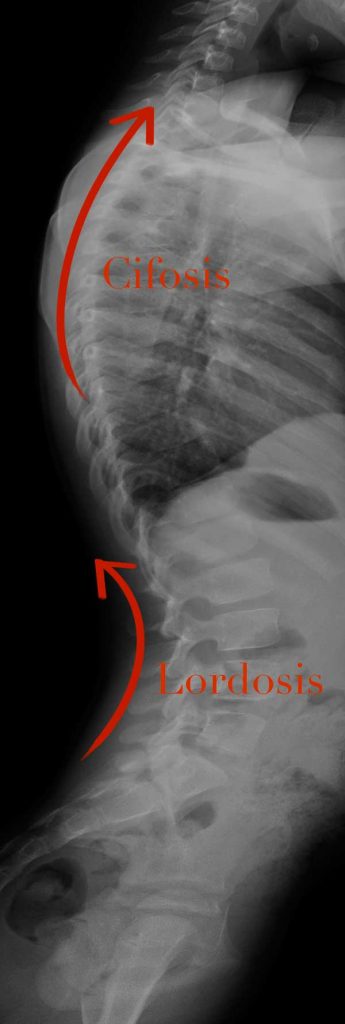

El doblarse hacia delante le llamamos cifosis. Si miramos la columna desde el lado, veremos que tiene unas curvas. Son normales, tenemos el tórax algo redondeado y la columna lumbar algo metida (todos somos un poco “culo pollo”). De este modo hablaremos de una cifosis torácica y de una “lordosis” lumbar. A los padres os preocupa la cifosis, es normal, es lo que se ve. A tu fisio le preocupará más la curva lumbar que tiene que ver en la forma que posicionas tu pelvis y afecta a la “postura global”.

La cifosis es cosa de los abuelos por acuñamiento de las vértebras, en niños habitualmente es una alteración postural, de dejarse caer hacia delante, pero cuidado, también existe alguna enfermedad que produce cifosis a los niños.

Los traumatólogos infantiles y nuestros compañeros de columna haremos unas maniobras sencillas para ver si la curva es flexible. Es decir, si el niño se estira y la curva desaparece será un problema postural, pero sin embargo, cuando se estira todo lo que puede y sigue habiendo algo de cifosis es que tendrá una cifosis “estructurada”.

Sin embargo, cuando aparecen vértebras acuñadas en los adolescentes, podemos tener una enfermedad llamada cifosis de Sheuermann. No es culpa del niño ni de los padres. Simplemente no puede ponerse absolutamente recto y siempre tendrá algo de cifosis. Alguno necesita incluso poner corsé, pero solo los casos peores.